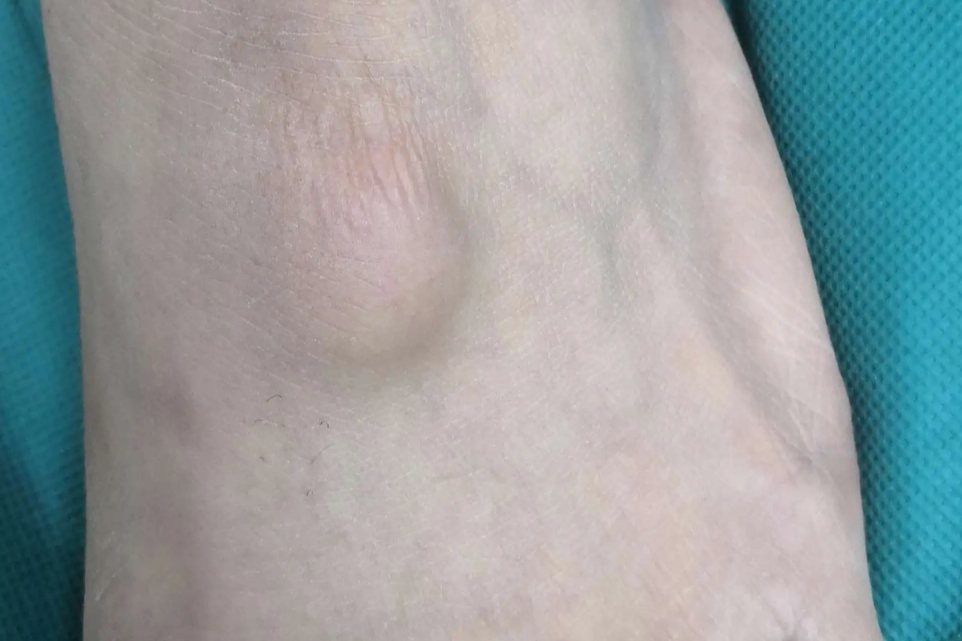

手背个凸起硬包不痛不痒可见于浅表性皮下脂肪瘤或腱鞘囊肿。浅表性皮下脂肪瘤表现为无痛性皮下结节;腱鞘囊肿为内含黏液性胶状物的圆形包块。

腱鞘囊肿

腱鞘囊肿主要发生在关节及腱鞘处,为圆形有弹性的囊性肿物,表面比较平滑。囊肿大小随时间改变,透光试验阳性,抽吸囊肿可见黏液性胶状物。